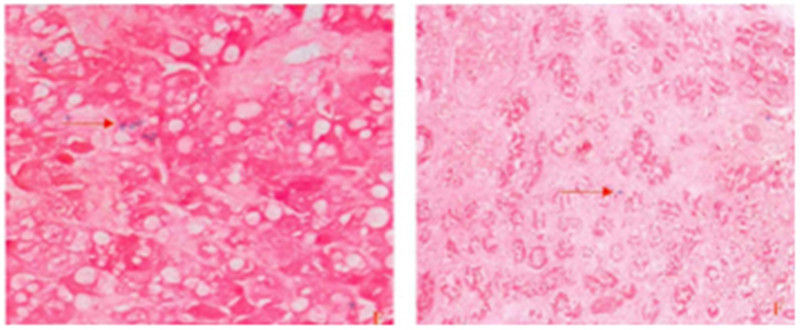

胶原有四型(Ⅰ、Ⅱ、Ⅲ、Ⅳ)区分并定量这四种胶原纤维,对于研究病变的发生机理和演变过程有一定的意义。利用胶原蛋白聚合及其缠绕螺旋排列不同的特点,使用天狼星红苦味酸染色法,在偏振光显微镜下,可以根据双折光性和着色的不同,分别显示出四型胶原纤维。普通光镜观察:胶原纤维呈红色,细胞核呈绿色,其他成分呈黄色。偏振光显微镜下观察:

Ⅰ型胶原纤维:红色或黄色,排列紧密,具强双折光性。Ⅱ型胶原纤维:多种色彩,疏松网状、弱双折光性。Ⅲ型胶原纤维:绿色、细纤维、弱双折光性。Ⅳ型胶原纤维:淡黄色、弱双折光性(基膜成分)。